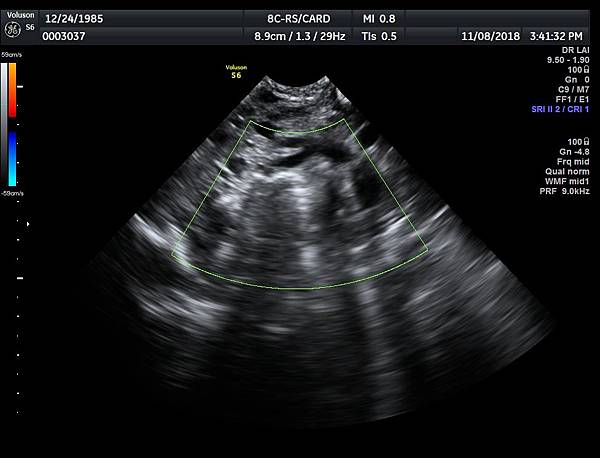

有一對夫妻因為我之前迷走性右側鎖骨下動脈(ARSA)的診斷而選擇孕兒診所,先生告知因為曾經有一個產前被我診斷ARSA的個案在他們醫院出生,他們花很久的時間才證實新生兒有ARSA,他覺得我很厲害,我有點不好意思,其實對專家而言,胎兒時期要診斷ARSA比新生兒容易,原因是胎兒時期超音波下,這條血管可以很清楚的被看到,它是從主動脈出來經過氣管的後面由左側繞到右側(附圖 1.),但是新生兒心臟超音波要看這條血管有困難,因為氣管擋住這條血管,醫師只能靠主動脈的第一個分支(brachiocephalic artery)沒有呈現 y 的特徵(附圖 2.),所謂 y 是brachiocephalic artery正常是會分出兩個分支(附圖 3.4.),一個是right common carotid artery,另一個是right subclavian artery,如果有迷走性右側鎖骨下動脈( ARSA ),就不會有正常的right subclavian artery,所以在新生兒的右頸部就不會看到 y的特徵,新生兒要直接看到迷走性右側鎖骨下動脈( ARSA)這條血管真的要花很多的時間(參考第51篇文章)。